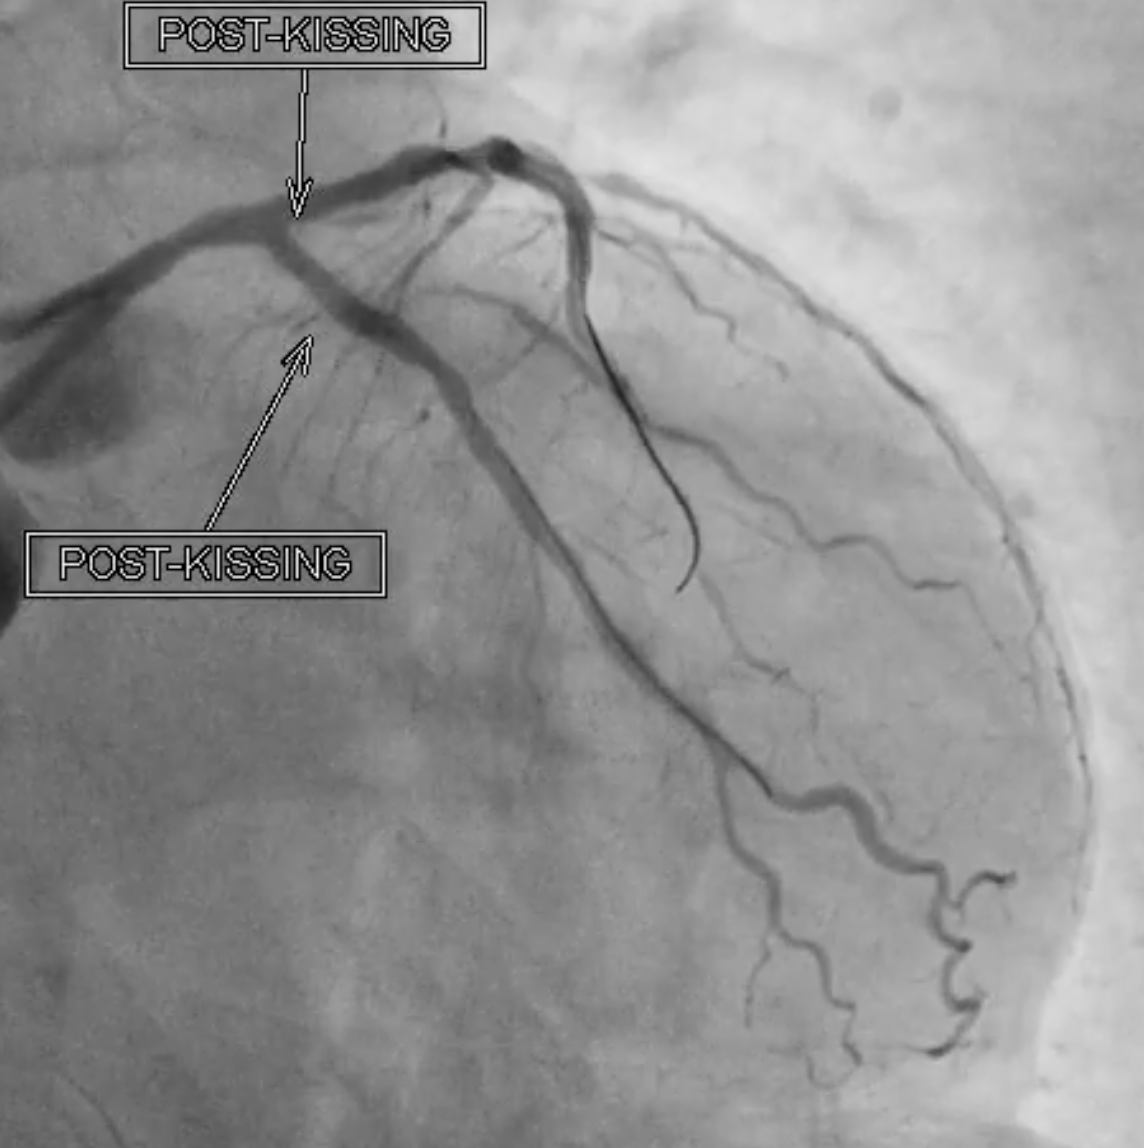

Under IABP (left femoral), PCI via right brachial with 6 Fr EBU 3.5. Runthrough to LAD, Sion Blue to LCX. Predilation of LM/pLAD with 2.0¡¿20 mm balloon; IVUS pullbacks. Further dilatation with 2.5¡¿20 mm NC for mLAD underexpansion, pLAD, and LM. oLCX de novo and pLCX edge ISR predilated with 2.5¡¿20 mm NC; LCX ISR treated with DCB 2.5¡¿20 mm. Szabo technique attempted for LM–LAD with a 3.0¡¿24 mm DES; the undeployed stent dislodged during repositioning and was deployed at the dislodgement site. IVUS showed 2–3 struts protruding into the aorta from the LM ostium and incomplete pLAD coverage. Post-dilation with 3.5¡¿20 and 2.5¡¿20 mm NC; DCB 3.0¡¿20 mm for pLAD uncovered plaque and mLAD proximal edge ISR. Final CAG: TIMI 3 flow.At 3 months, staged PCI via right radial with 6 Fr EBU 3.5. Sion Blue ES to distal LAD. IVUS: mLAD stent underexpansion (MSA <2.0 mm©÷); wire not through struts. IVL 3.5¡¿12 mm initially could not cross LM; after guide exchange (JL 3.5, then EBU 3.0/3.5), IVL advanced to mLAD and delivered 100 shocks, producing a ring crack and area gain. Further dilation with 3.0¡¿20 and 3.5¡¿20 mm NC. IVUS: pLAD type B dissection without flow limitation. DCB 3.5¡¿40 mm to p–mLAD. LM ostial stent further dilated with 3.5¡¿20 mm. Final CAG: TIMI 3 flow.